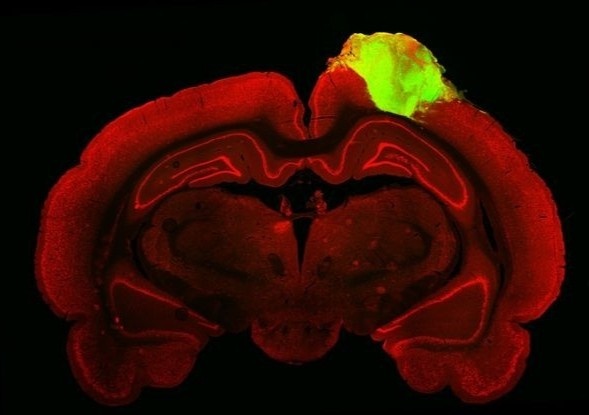

Để phát triển “bộ não nhỏ” của con người, các nhà nghiên cứu đã sử dụng tế bào gốc cảm ứng vạn năng được biến đổi gene để biểu hiện protein huỳnh quang xanh lá cây (green fluorescent protein), loại protein bao gồm 238 amino axit.

Tế bào gốc cảm ứng vạn năng được tạo ra từ các tế bào gốc trưởng thành qua quá trình tái lập trình bộ gene. Chúng có thể phát triển thành nhiều loại tế bào khác nhau. Protein huỳnh quang xanh lá cây mang lại cho các organoid não khả năng phát huỳnh quang.

cay ghep anh 1

Hình ảnh mô học của não chuột với cơ quan vỏ não người được cấy ghép (màu xanh lá cây). Ảnh: Cell Stem Cell.